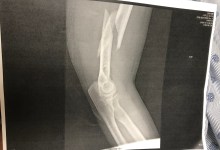

A homeless woman suffers a badly broken arm during her struggle with an officer.